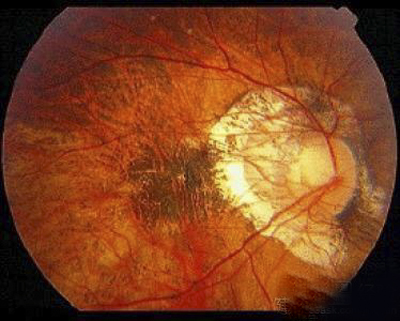

A:飛蚊症是指眼前有飄動的黑影,尤其是看白色背景的時候症狀更加明顯,同時有時候有些人會伴有閃光感,眼前一亮一亮的症狀,引起的原因主要是玻璃體液化和後脫離。絕大多數的飛蚊症都是生理性,但是有大約20%的飛蚊症,可能是病理性,具有威脅視力下降的情……

A:飛蠅症又稱飛蚊症和玻璃體混濁,是指玻璃體內出現不透明體,造成患者視物出現模糊。人出生時玻璃體呈凝膠狀態,是重要的屈光介質,正常的玻璃體隨著年齡逐漸出現液化,從而導致玻璃體混濁。此外,一切玻璃體混濁是由於病理原因所導致,例如玻璃體出血、葡萄……

A:眼前出現飛蚊的症狀往往是因為玻璃體發生了液化、變性和混濁,通常情況下玻璃體的混濁,比較多見於近視眼的人和年歲比較大的中老年人,還要特別重視的一個問題是當眼底有病變發生的時候,也會出現玻璃體的混濁、玻璃體混濁的加重,這時候眼前飛蚊的症狀需要做……